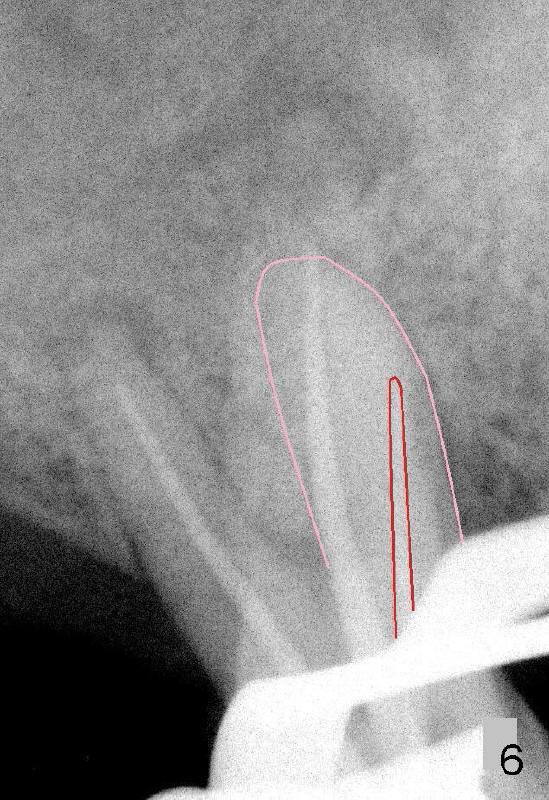

上一集我们讨论右上第一磨牙好像有MB2(图五),因为MB主牙胶尖(图六红线)不在那个根(粉红色)的当中,但是MB2根管口又找不到。敦促病人去拍摄CT,他是Emory大学教授,说有空才能去办。初步根管扩大冲洗,症状改善不少,但是心里不踏实,害怕他不去拍摄CT。

20/.06; DB: 30/.06; P: 40/.06,与图五,图六对比。总之,没有CT,事倍功半。

files达到不了工作长度(WL),但是衡量自己能力和时间,并没有进一步努力。时间还花在增加远中颊侧根和鄂侧根WL(其实没有必要,比较图四,图七),结果那里糊剂超充。副牙胶尖还充到原来ledge那里(图七箭头),如果第一次根管治疗就有CT指导,这样事情就有可能避免。图八显示根尖三分之一弯曲根管(黑线)与第一次根管扩大部分(红线)关系。